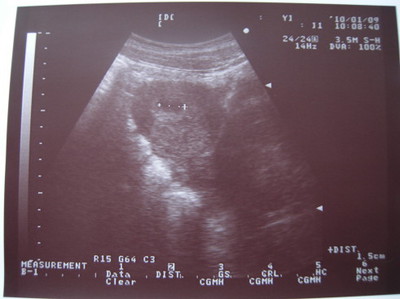

寶貝: 第五週。你已經1.5cm大了,逐漸朝人體的形狀發育。馬麻身體的不適,不曾和緩。 每到傍晚,馬麻的肚子開... (詳全文)